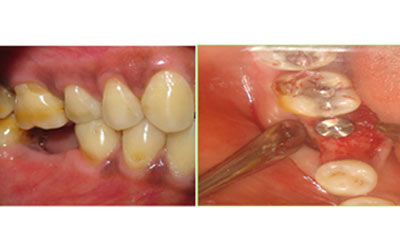

Oral maxillofacial surgery is another prominent specialty at Venkateshwar hospital, Delhi. Our team of skilled surgeons is trained in diagnosing and treating complex oral and facial conditions. Whether you require dental implants, corrective jaw surgery, facial trauma treatment, or removal of impacted teeth, our oral maxillofacial surgeons provide expert care and utilize advanced techniques to ensure optimal outcomes and a speedy recovery.

Painless Root Canal Treatment:

At Venkateshwar Hospital,Delhi, painless root canal treatment is performed with precision and care. Using advanced local anesthesia techniques, we ensure minimal discomfort during the procedure. The dentist gently removes the infected pulp, cleans the canal, and seals it with biocompatible materials. Our modern equipment and experienced practitioners ensure efficient and virtually pain-free treatment. Patients can resume normal activities shortly after the procedure, experiencing relief from the initial pain caused by the infection.

Laser root canal treatment is considered to be the future of dental care. Utilizing cutting-edge laser technology, weoffer a minimally invasive approach. Laser dentistry can be seamlessly integrated with traditional root canal techniques to enhance the efficacy of removing infected pulp and eradicating bacteria, thus preventing the likelihood of infection recurrence. The procedure often involves the utilization of a laser drill to gain access to the inner chamber, accompanied by a soft-tissue laser for thorough sterilization of the tooth's structures. This includes targeting intricate areas like the dentinal tubules, which may be challenging to treat using conventional methods. Laser root canal treatment provides a more precise means of exposing the tooth's pulp while conserving a greater portion of the healthy tooth structure. Additionally, the laser can be employed to reshape the dentinal walls of the canal if needed. Notably, this technique minimizes friction throughout the process, resulting in a significant reduction in discomfort and pain for the patient.